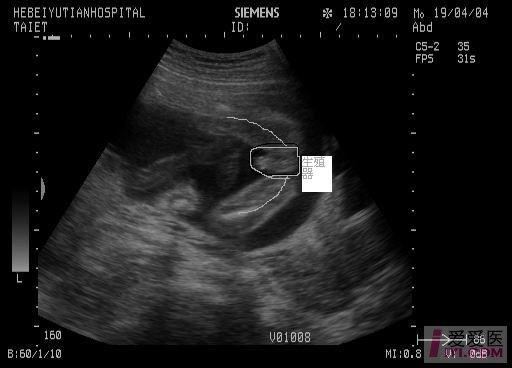

二维超声:胎儿双侧阴囊内可见睾丸回声(图 1).

胎儿隐睾可能?

原创几例胎儿